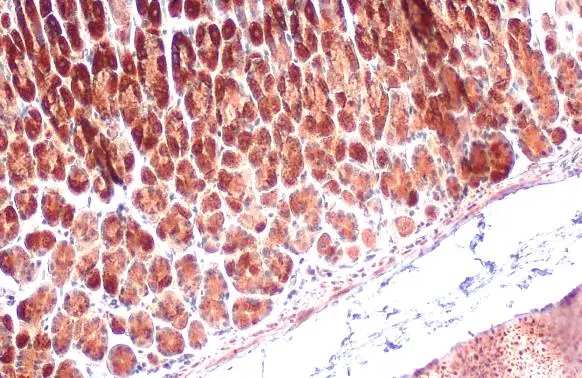

ApplicationsImmunoFluorescence, ImmunoPrecipitation, Western Blot, ImmunoCytoChemistry, ImmunoHistoChemistry, ImmunoHistoChemistry Paraffin

- ApplicationsImmunoFluorescence, ImmunoPrecipitation, Western Blot, ImmunoCytoChemistry, ImmunoHistoChemistry, ImmunoHistoChemistry Paraffin